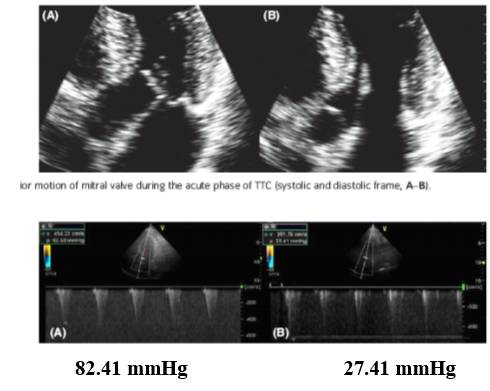

应激性心肌病合并左室流出道梗阻艾司洛尔的有效性和安全性:多中心注册研究

[11]

研究概况

◆本研究的目的是评价超短效高选择性的β受体受体阻滞艾司洛尔治疗对应激性心肌病合并左室流出道梗阻患者的有效性和安全性

◆96例应激性心肌病患者,其中10例伴有左室流出道梗阻,9例应用艾司洛尔治疗

◆平均随访202±42天

艾司洛尔显著降低左室流出道压差

与用药前比较,应用艾司洛尔后左室射血分数提高(35± 9% vs 53±4%, P = 0.001);左室流出道压差降低(47.6±16.6 mmHg vs 18.2±2.3 mmHg(P = 0.0091)收缩压从123.8±29.1降低至 112.6±12.7 mmHg(P = 0.1537)

研究意义

◆应激性心肌病患者存在左心室流出道梗阻时,使用正性肌力药物或血管扩张剂可能有严重不良作用,这类药物会加重这种梗阻,促使休克发生

◆本研究结果证实了艾司洛尔对在这一类患者的有效性和安全性具有重要的临床意义

◆应激性心肌病的预后通常良好,病情多在数周或数月内完全恢复,短期应用艾司洛尔有助于患者度过急性期